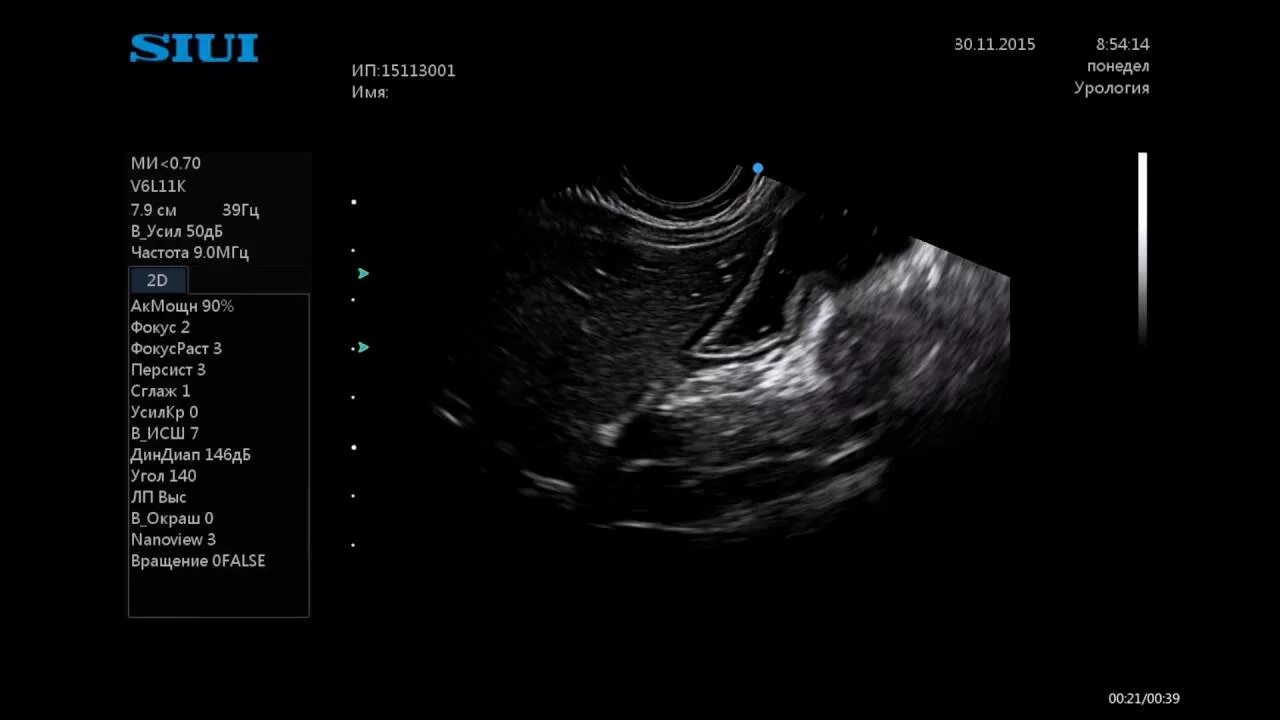

Как выглядит узи живота